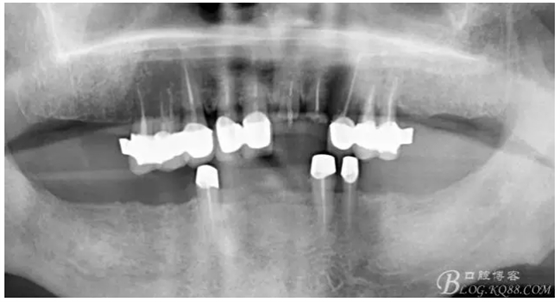

上牙出現(xiàn)了不同程度的牙齦萎縮

缺損太多 是必須用金屬樁修復(fù)的,

還要有足夠的牙本質(zhì)肩領(lǐng),大家現(xiàn)在可以看到患者的下頜套筒冠還是非常好的

雖然牙根折斷了,但是從這張片子可以看出我們的套筒冠還是很堅(jiān)挺的,有牙齦的退縮,但是牙槽骨致密程度非常好,值得欣慰